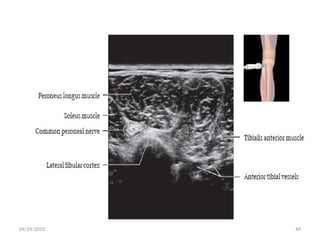

 Ultrasound

 Short axis: A typical “honeycomb” appearance with hypoechoic

fascicles and surrounding echogenic perineurium

 Long axis: Parallel hypoechoic tracts of uniform caliber.

 Distortion of this uniform appearance suggests pathology

• Trace medium-sized nerves by following their course as they

branch from their parent.

• Small (1-2 mm) nerves are difficult to identify and location

may only be inferred by adjacent vessels.